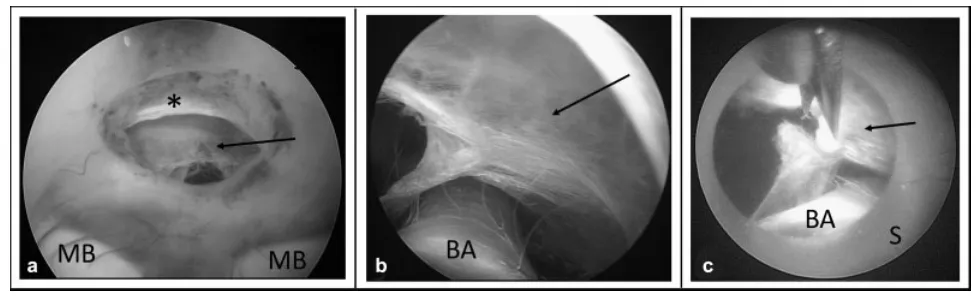

合并桥前蛛网膜的内镜下第三脑室造瘘术。 (a) 第三脑室造瘘术后,透过宽敞的脑室造瘘口及已开窗的Liliequist膜可见深部蛛网膜。 (b) 将LITTLE LOTTA脑室镜的鞘管经脑室造瘘口向前推进后,可见基底动脉及蛛网膜。 (c) 在内镜鞘保护基底动脉的同时,用剪刀切开蛛网膜。箭头指示桥前蛛网膜;星号指示Liliequist膜。缩写:BA,基底动脉;MB,乳头体;S,内镜鞘。